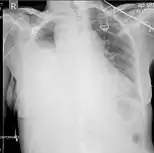

Chest MRI showing a hemothorax in a 16-day-old infant